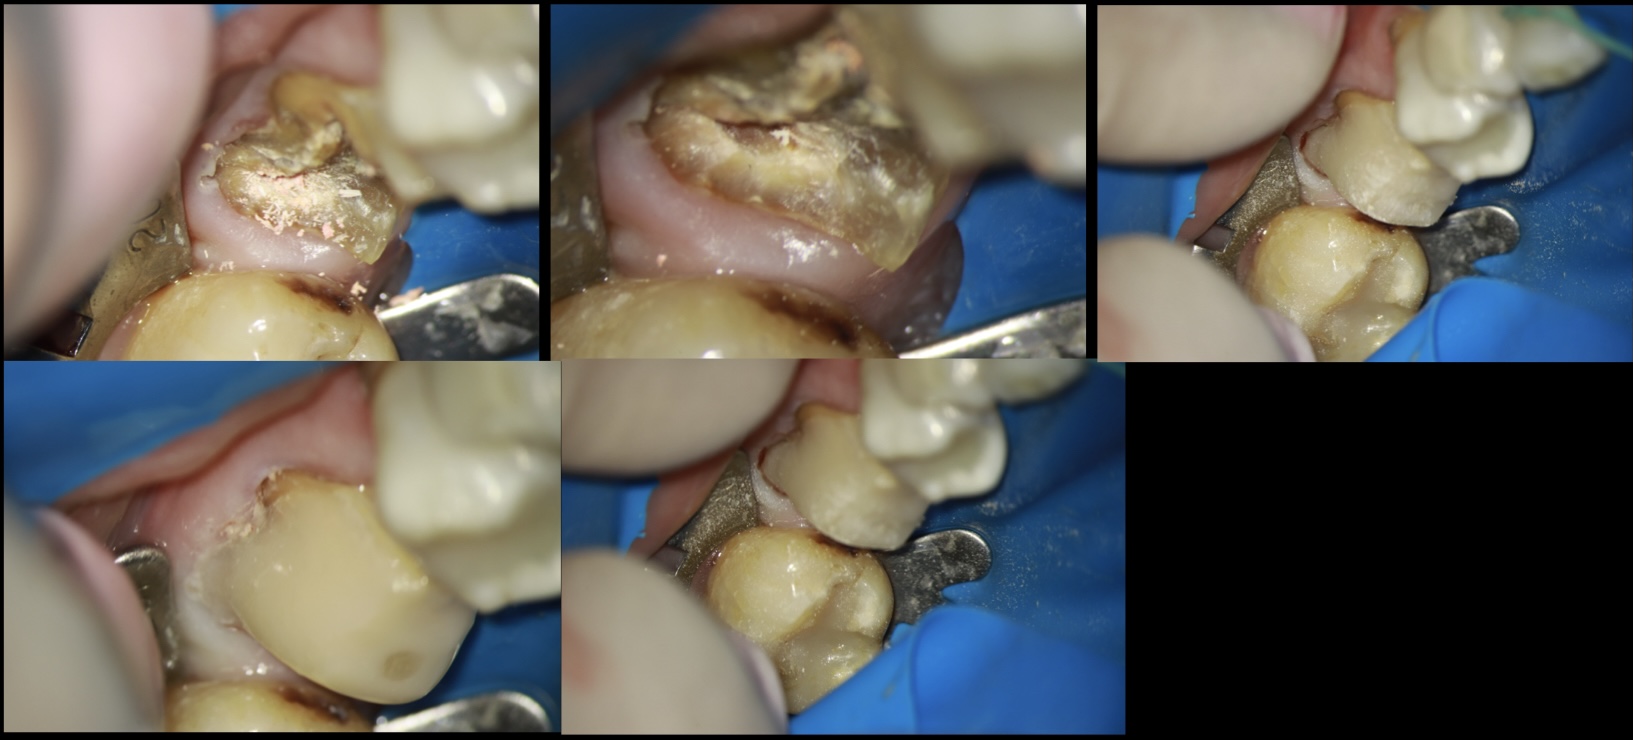

Cáries bastante profundas, muitas vezes atingindo áreas interproximais, podem dificultar o isolamento absoluto de um dente na hora de ele necessitar de um tratamento endodôntico ou retratamento endodôntico. Muitas variações das técnicas de isolamento absoluto podem ser feitas para conseguir isolar estes dentes destruídos.

Porém, em muitos casos estes dentes podem ser os últimos da arcada e você ter dificuldade em colocar um grampo sobre o próprio dente para fazer o isolamento absoluto ou usar alguma técnica de isolamento a distância.

Muitas vezes o procedimento inicial deve ser feito com isolamento relativo, pois o preparo pode estar bastante subgengival.

1. O dentista deve remover todo o tecido cariado com brocas esféricas diamantadas em alta rotação ou brocas carbide de baixa rotação de calibres compatíveis com a necessidade do que se precisa remover.

2. Se houver tecido gengival edemaciado invadindo o espaço dentário, este tecido pode ser removido com bisturi elétrico ou laser de alta potência.